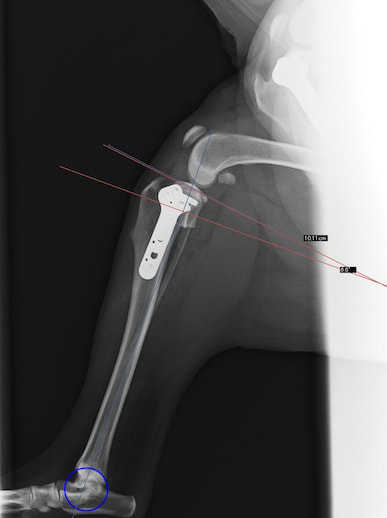

雑種犬 推定10歳 避妊雌

本症例は、走った後に左後肢を挙上していることを主訴に来院されました。触診時に左膝関節のクリック音を聴取、レントゲン検査にて左脛骨の前方変位が認められました。術中に、前十字靱帯の断裂及び内側半月板の損傷、内側の軟部組織の顕著な腫脹を確認。半月板切除、TPLOを実施しました。周囲組織への炎症の波及もあったため回復に時間を要しておりますが、徐々に跛行頻度は減少傾向にあり、現在も経過観察中です。術前に約29°あったTPAは術後に約10°まで矯正されました。

術前写真

術後写真

手術前後のTPA(脛骨高平部の角度)を測定しています。

約29°から約10°へ矯正されています。